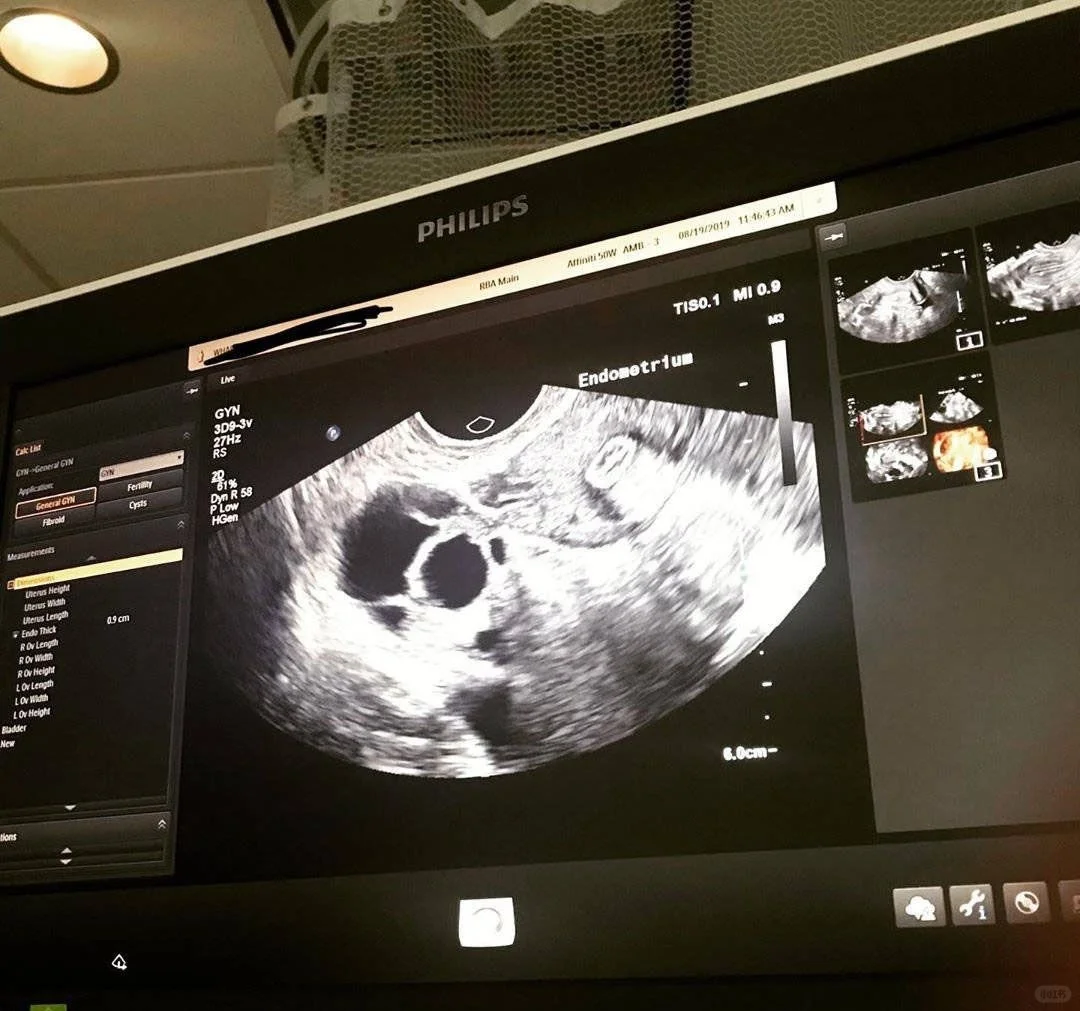

第一步,试管婴儿国内前期检查是非常重要的!从最基础的性激素六项开始,验激素六项、肝功能、四毒、血常规、肾功能还要定期去做B超各种抽血验各项功能以及分泌物。根据国内检查报告,医生要根据每个人不同的情况开药的,虽然我当时也是比较着急进周,但是前期检查急不来。

在月经刚来第一天,我就赶紧定了机票隔天就飞泰国。与医生见面后,开始试管婴儿促排,每天一针促排针,一共打了10天打得我看见针就怕,打针天数长短因人而异吧。我看有些人才打七八天。取卵手术,是我长这么大,第一次经历全麻无知觉的手术。提心吊胆了几天,踏如手术室看到各种仪器的那一刻,心里是很恐惧的,但是想想有些人没有麻醉的都能做了,我这种全麻的眼一闭就过去了!

取完卵后要等差不多一周出囊胚报告。等报告这段时间,我在国内就一边工作一边服药。取卵后又出现了一次假性月经,也叫撤退性出血,由于促排使用了激素药,会影响正常周期。问了医生其实是正常情况,大家不用那么紧张。

至于胚胎移植后,以及胚胎着床阶段,这个阶段就是看试管成功与否的阶段。我也简单说说吧。我是胚胎移植7天,去医院做的抽血验孕查hcg,还好我的宝宝很坚强,与我也很有缘分,成功着床了。提醒一下,这段时间一定的特别注意调整好状态,特别是心情不应有什么过大的起伏,少剧烈运动多休息。